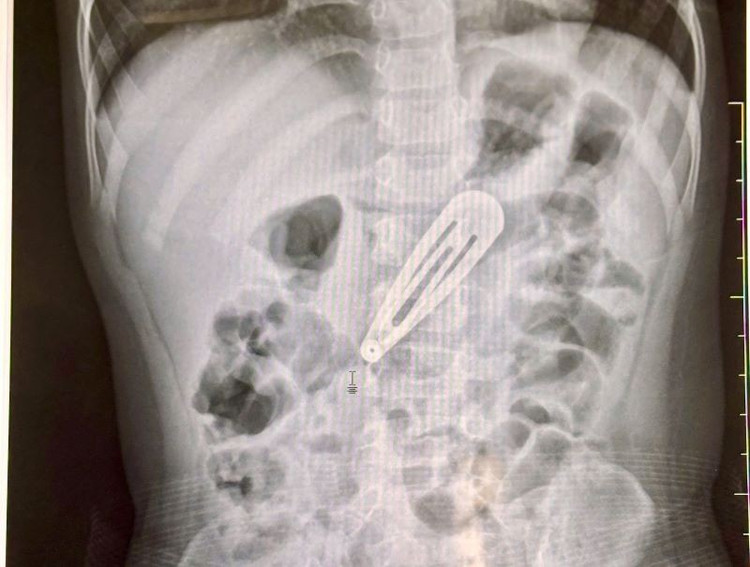

Chụp X-quang ghi nhận hình ảnh một dị vật kim loại nằm trong ổ bụng - Ảnh BVCC

Sau khi thăm khám lâm sàng và chụp X-quang bụng, các bác sĩ ghi nhận hình ảnh một dị vật kim loại nằm trong ổ bụng, tương ứng vị trí dạ dày của bé. Bé nhanh chóng được chuyển sang Trung tâm Nội soi tiêu hóa và Thăm dò chức năng để tiến hành nội soi can thiệp lấy dị vật ra ngoài.